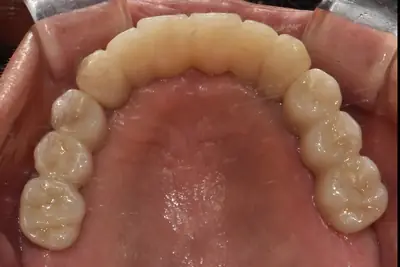

치과 치료를 두려워하는 분들을 위해, 진정요법을 활용한 사례를 소개합니다. 부산에 거주하던 60대 여성 환자가 치아가 많이 손상되어 임플란트와 브릿지 치료를 받았는데, 병원 트라우마와 공포로 어려움이 있었어요. 의식하 진정요법을 통해 깊은 낮잠 같은 상태에서 안전하게 치료를 받았고, 수술 과정도 성공적이었어요. 이 방법은 전신마취보다 안전하고, 환자도 큰 두려움 없이 치료를 마칠 수 있어요. 치과 공포증이 심한 분들도 전문가와 상담 후 진정요법을 고려해보시면 좋겠습니다.